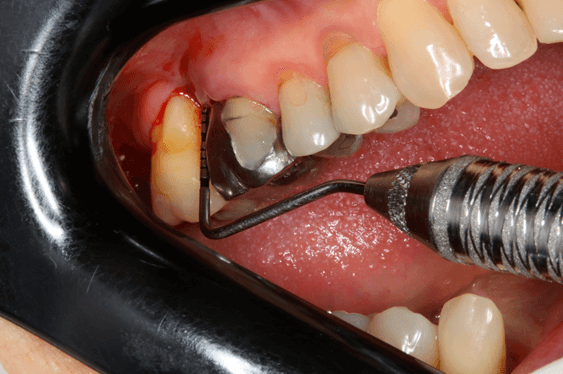

Avaliamos o desempenho do biomaterial de hidroxiapatita com colágeno tipo I (Extra Graft XG-13®) na manutenção do volume alveolar.

A aplicação como o caso clínico abaixo se mostrou uma técnica acessível a todos cirurgiões dentistas, pois se trata de um procedimento de simples execução e acessível. Logo, deveria constar na clínica diária.